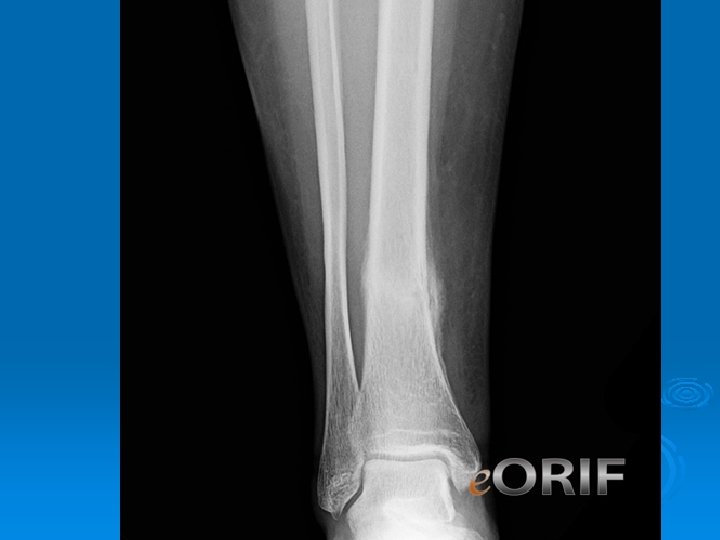

Stress Fracture • Bone Scan MRI

Stress Fractures Protected or Nonweightbearing Long Term Issues • • • Nutrition Hormonal Training